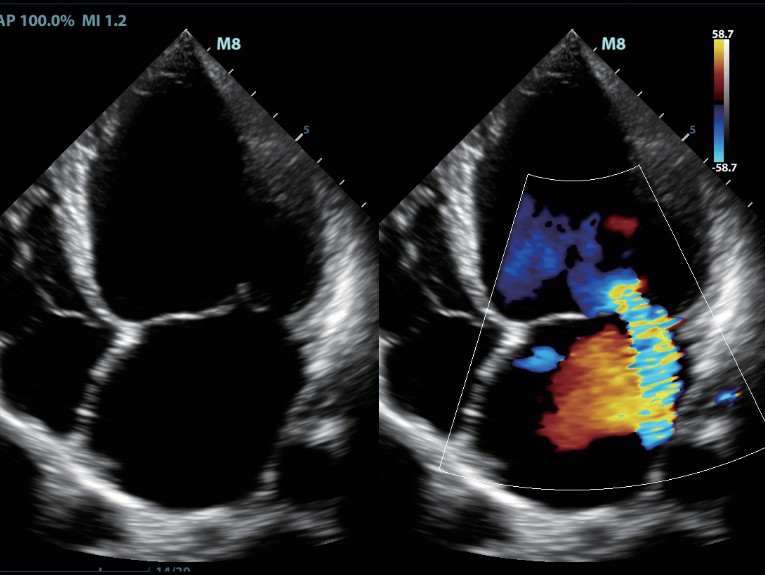

Клинические изображения